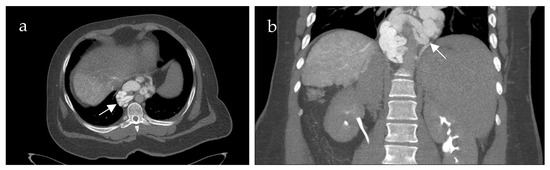

3.3. CT-SMPG Compared to CECT

Additional CECT in the portal venous phase was available in 18 of 21 patients. Table 1 summarizes the diagnostic differences of CT-SMPG and CECT concerning detection of thrombosis of splanchnic veins (SMV, SV and confluence) and varices. CT-SMPG and CECT were quite similar in detecting PVCT, SMV and SV thrombosis whereas CT-SMPG was superior to CECT in detecting varices, gastropathy and venous congestion. Figure 2 shows an example of the same patient comparing CECT and CT-MPG.

Figure 2. 70-year-old female patient with portal hypertension due to chronic portal vein thrombosis. Axial images of contrast-enhanced computed tomography (CECT) (a) and computed tomography mesenterico-portography (CT-MPG) after contrast injection into the superior mesenteric artery (b). The CECT image shows diffuse contrast enhancement of the gastric wall (a) (white arrow). CT-MPG detects the partial hyperperfusion of the gastric wall (white arrow) and the cavernous transformation of the portal vein (white arrowhead (b)).